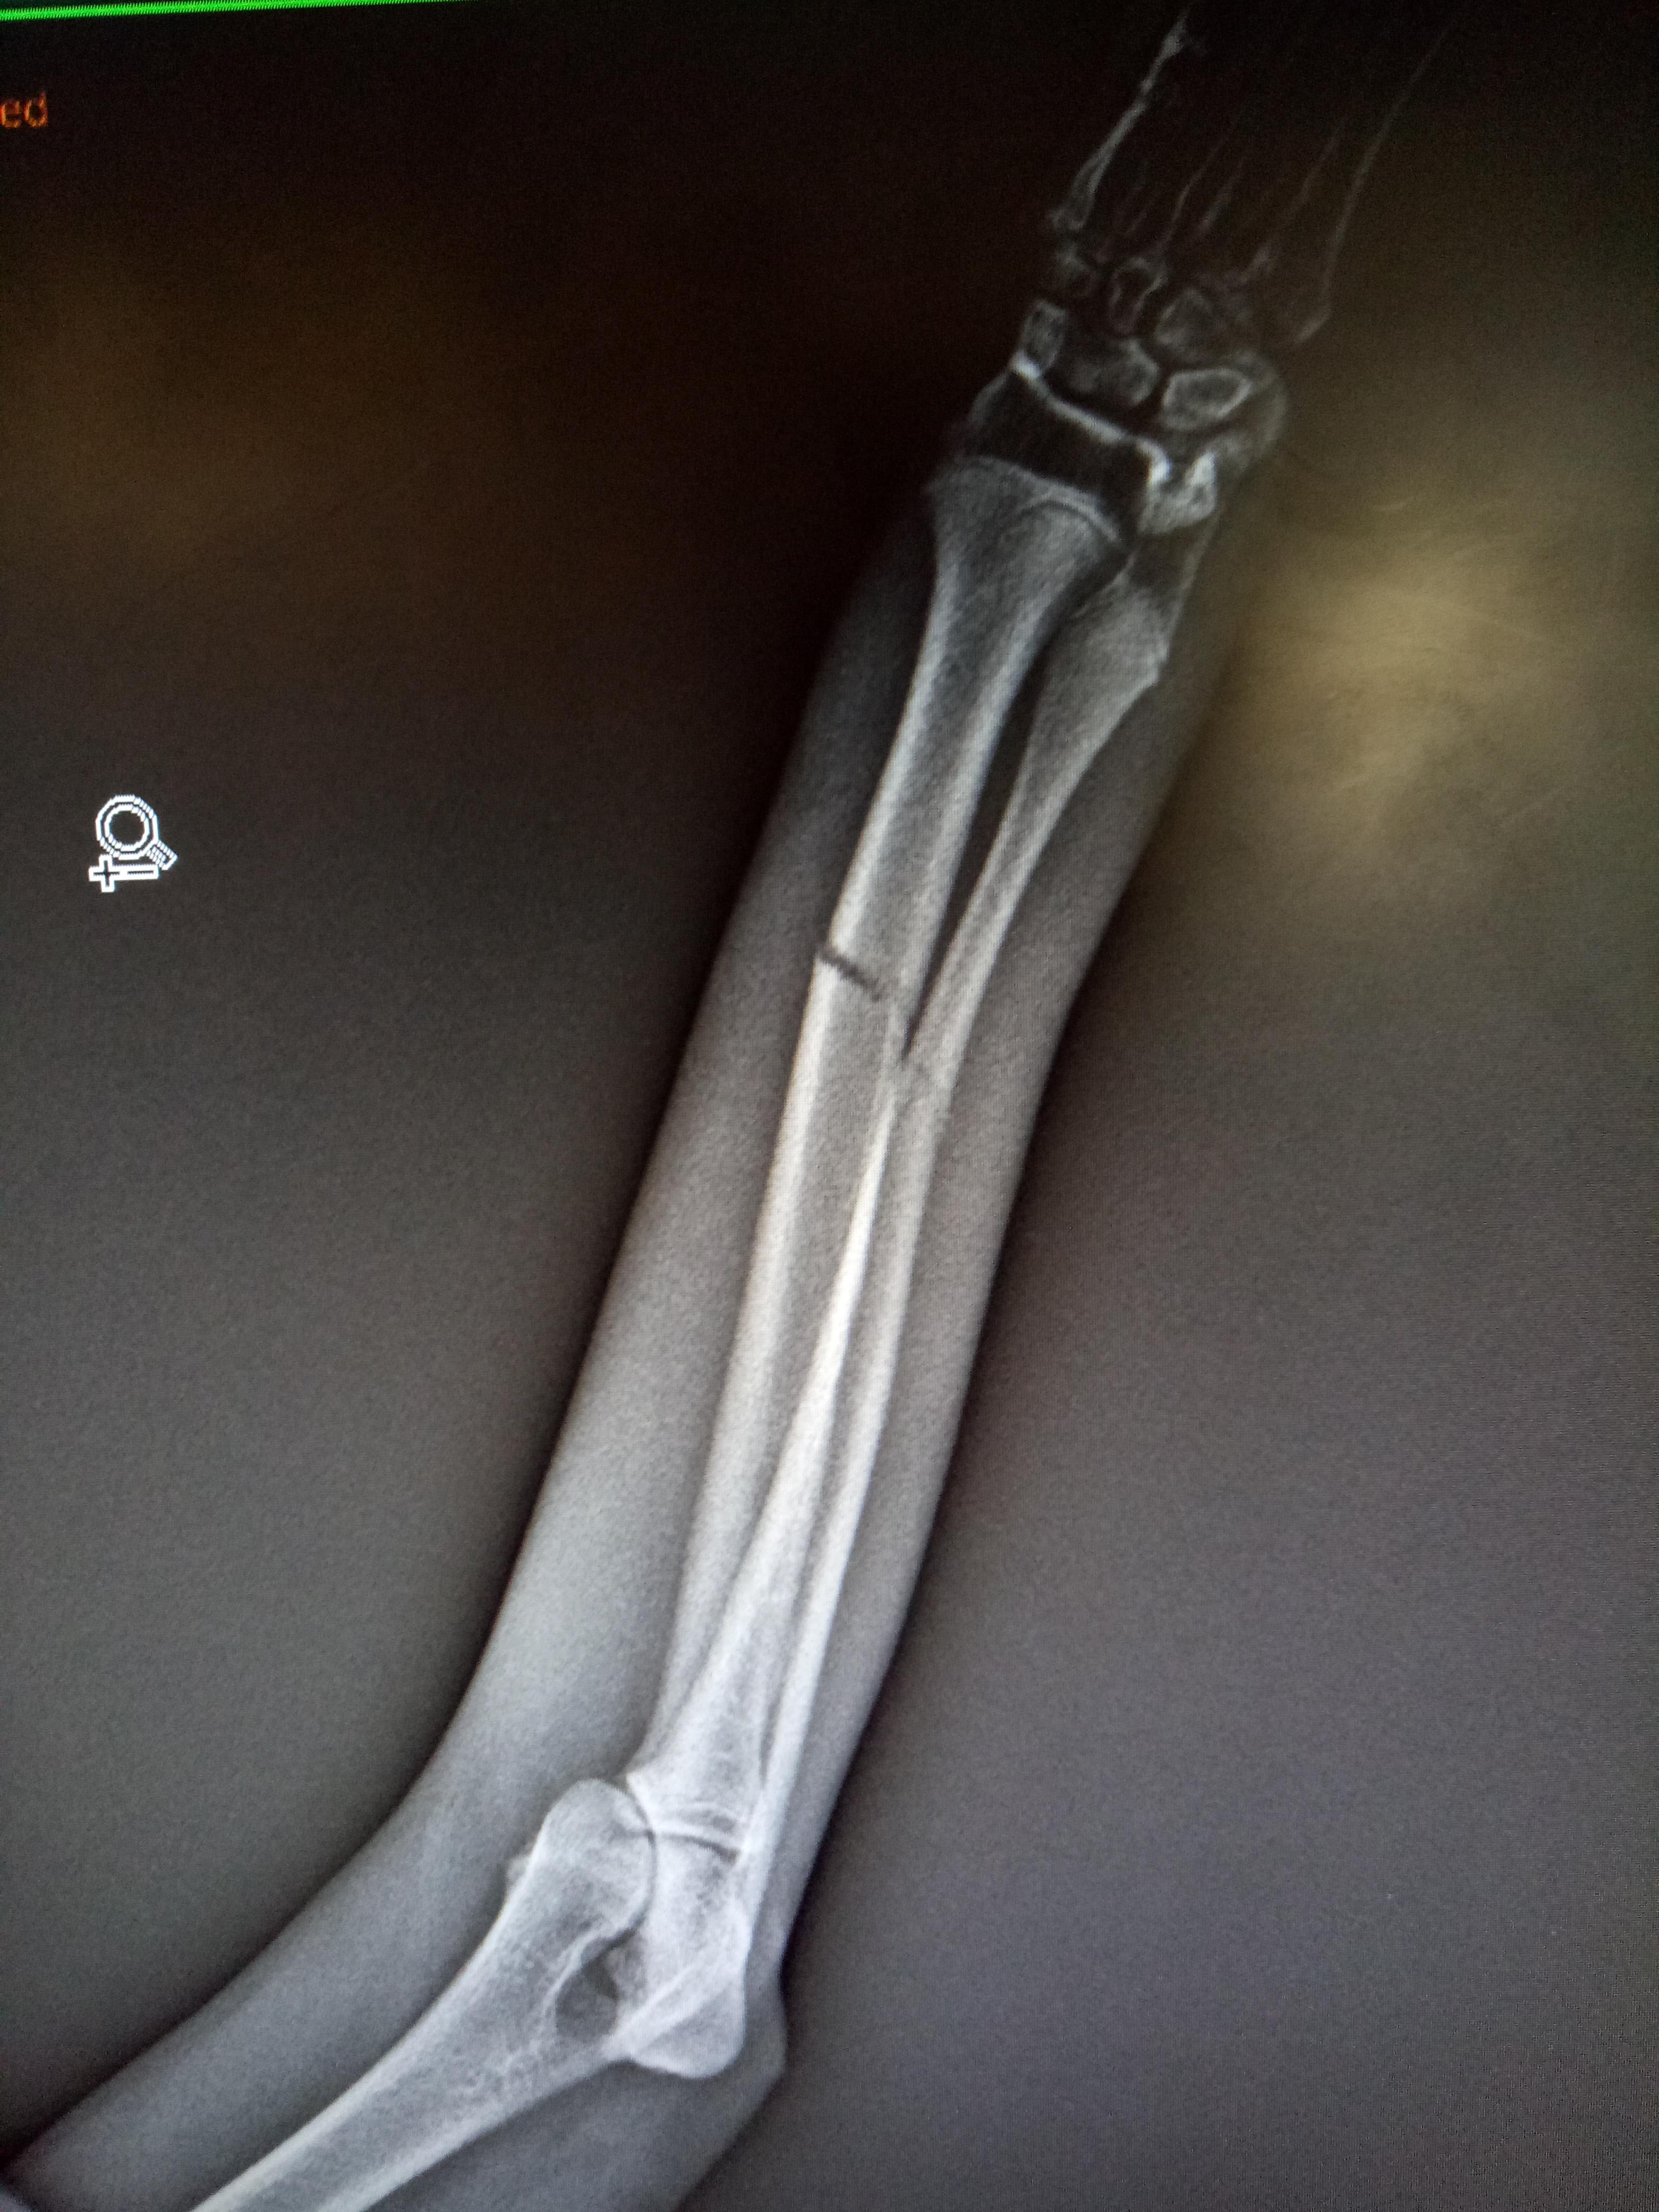

Hi! I am concerned with my dog, his name is divi. As you can see from my attached photos, he just got a bandage last Friday because he had his right radio-ulna fractured. Now, his foot has non-stop swelling and hyperemia. What should I do? I tried to loosen up the bandage but he don't want me to touch it, he keeps on biting and attacking me.

The swelling is very bad. You are correct to be concerned. I suggest you get him back to the vet ASAP to have the bandage removed and replaced. He is a lot of pain for sure which is why he is trying to bite. The fracture is unstable at this stage so you can't just take the bandage off and leave it like that. The vet should put on a full length cast that incorporates the foot. If you don't get this treated immediately the blood/nerve supply may end up being compromised to the foot. This is an emergency.